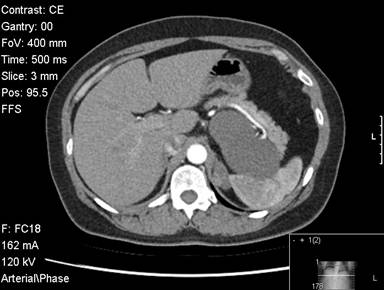

A fifty-two-year-old female was evaluated for abdominal pain. She had a vague history of upper and left sided abdominal pain for 6 months. An ultrasound showed a cystic lesion in the left upper abdomen. A CT scan subsequently confirmed the presence of a large 10 cm cystic lesion in very close proximity to the spleen and the pancreas. The lesion reached close to the neck of the pancreas. The lesion involved the mid-body / tail of the pancreas, was abutting against the spleen (Figures 1 and 2). There was close proximity to the splenic vein, although the vein was patent. The splenic artery was close but seemed uninvolved (Figure 3). The cyst wall was uniform. There were no internal septations or any other features to suggest an intracystic solid component or bleeding. There were no calcifications with the cyst. The rest of the pancreas appeared normal with no evidence of pancreatitis. There were no gall stones or any other biliary abnormality. Clinicoradiologically it was felt to be a large cyst possibly a splenic cyst. However given the fact that she was symptomatic, we decided to proceed with a laparoscopic resection. All her blood tests including tumour marker profile (CA 19-9 and CEA) were normal. She underwent a laparoscopic distal pancreatectomy with splenectomy. At laparoscopy we discovered a large cystic lesion occupying the lesser sac and abutting against the spleen. The pancreas could not be separated off the cyst. We completely mobilised the stomach off the cyst and the pancreas, to completely expose the pancreas with the cyst in the lesser sac. We completed a distal pancreatectomy with splenectomy laparoscopically, with complete enbloc excision of the cyst (Figure 4). Post-operative recovery was uneventful and the patient was discharged 4 days following surgery. Gross pathology showed a 90x50x60 mm cystic lesion, attached to and arising from the inferior and posterior aspect of the pancreas. On pathology the rest of the pancreas appeared normal and the splenic capsule was not breached. The histology of the cyst showed the presence of pseudo stratified ciliated columnar epithelium , overlying some connective tissue (Figure 5; H&E, magnification x10) .Similar features were confirmed on the high powered images of the cyst wall as well (H&E, magnification x20). Based on these characteristic and rather unusual histological features, the diagnosis of a ciliated foregut cyst of the pancreas was established.

Figure 3. Relation of the cyst to the splenic artery. |